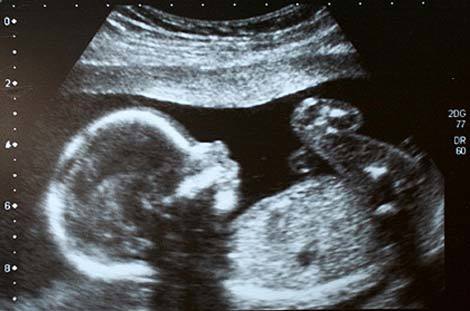

Cứu thai nhi trong tử cung

Y học đã có những bước tiến lớn đến mức ngày này, bạn thậm chí có thể nhận được các liệu pháp chữa trị tiên tiến từ khi chưa lọt lòng mẹ. Đứa con chưa ra đời của Kylie Bowlen, người Australia, đã là đối tượng phẫu thuật khi còn trong tử cung. Các bác sĩ đã tiến hành phẫu thuật để ngăn chặn các túi ối vốn đang cắt giảm lưu lượng máu đến chân của bé khi em mới chỉ dài 17,8cm.

Tái sinh bào thai

Gia đình McCartney ở Texas, Mỹ từng sợ điều tồi tệ nhất khi phải đối mặt với tin tức rằng, đứa con chưa sinh của họ đang phát triển trong tử cung cùng với một khối u chết người. Tuy nhiên, các bác sĩ đã thực hiện một cuộc phẫu thuật để cứu đứa trẻ chưa chào đời, trong đó bao gồm cả việc đưa bào thai ra khỏi cơ thể của mẹ và loại bỏ khối u. Thai nhi sau đó được đưa trở lại vào tử cung để tiếp tục phát triển như bình thường.